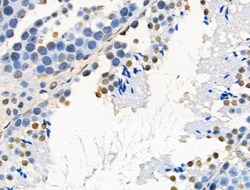

Invitrogen™ Phospho-AKT1 (Ser124) Polyclonal Antibody

Antibody detects endogenous levels of AKT1 only when phosphorylated at Ser124.

| Immunohistochemistry (Paraffin), Western Blot, Immunocytochemistry | |

| Human, Mouse, Rat | |